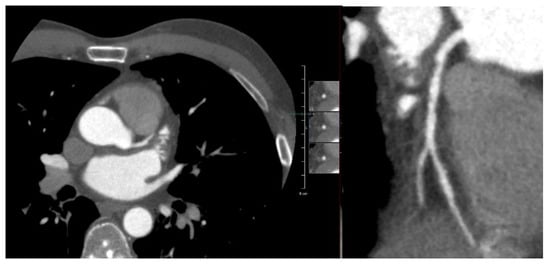

Appendix A.1. Patient A. Male, 46 Years

Appendix A.2. Patient B. Male, 45 Years